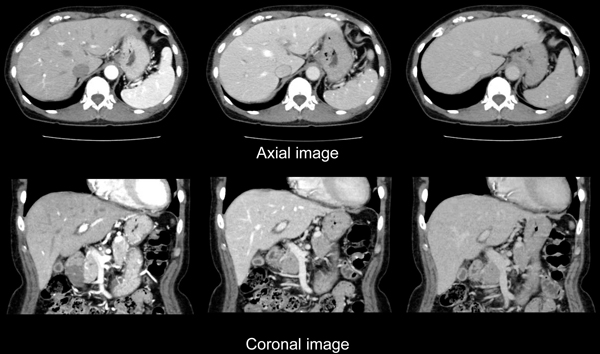

内臓脂肪測定検査

腹部単純CT検査の画像を利用して、体脂肪面積や皮下脂肪面積を計測し、それぞれの蓄積を観察できます。